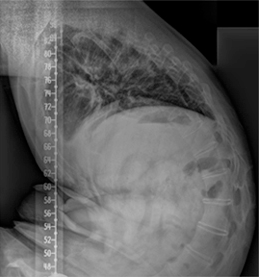

정상적으로 흉추는 기립 측면상에서 20~45도의 후만을 이루고 있습니다. 흉추 후만의 첨부는 제 7 흉추에 위치하며 흉추 후만각은 Cobb 방법상 제 4~12 흉추 사이의 각도를 측정합니다. 일반적인 방사선적 진단 기준으로 Schmorl 결절, 불규칙한 척추 종판, 추간판 간격의 협소를 동반한 적어도 3개 이상의 인접 척추의 5도 이상 설상변형이 제시됩니다. 척추 후만은 경직성으로 신전 시에도 변형이 남아 있으며 신전 시 측면 사진을 이용하여 만곡의 경직도를 가늠할 수 있습니다. 전후방 사진상 다양한 정도의 측만이 환자의 약 1/3에서 동반되어 있으며 척추 전방전위증이 동반된 경우도 있습니다. 동반된 척추 전방전위증은 대부분 협부형으로 대상성 요추 과전만으로 인한 추궁 협부의 긴장으로 설명됩니다. 변형의 유형에 따라 흉추형과 흉요추형으로 나눌 수 있으며 흉추형인 제 1형이 더 흔한 형으로 만곡의 첨부가 제 6~8 흉추 사이에 위치하며 흉추 후만증과 함께 경추와 요추의 과전만을 보이고, 흉요추형인 제 2형은 보다 드물며 만곡의 첨부가 제 10 흉추와 제 1 요추 사이에 위치한 흉요추부나 요추부의 후만증을 보입니다. 흉요추형이 보다 유연한 만곡을 가지며 늑골의 지지가 없으므로 만곡이 진행하는 경향을 보입니다.

방사선학적 소견